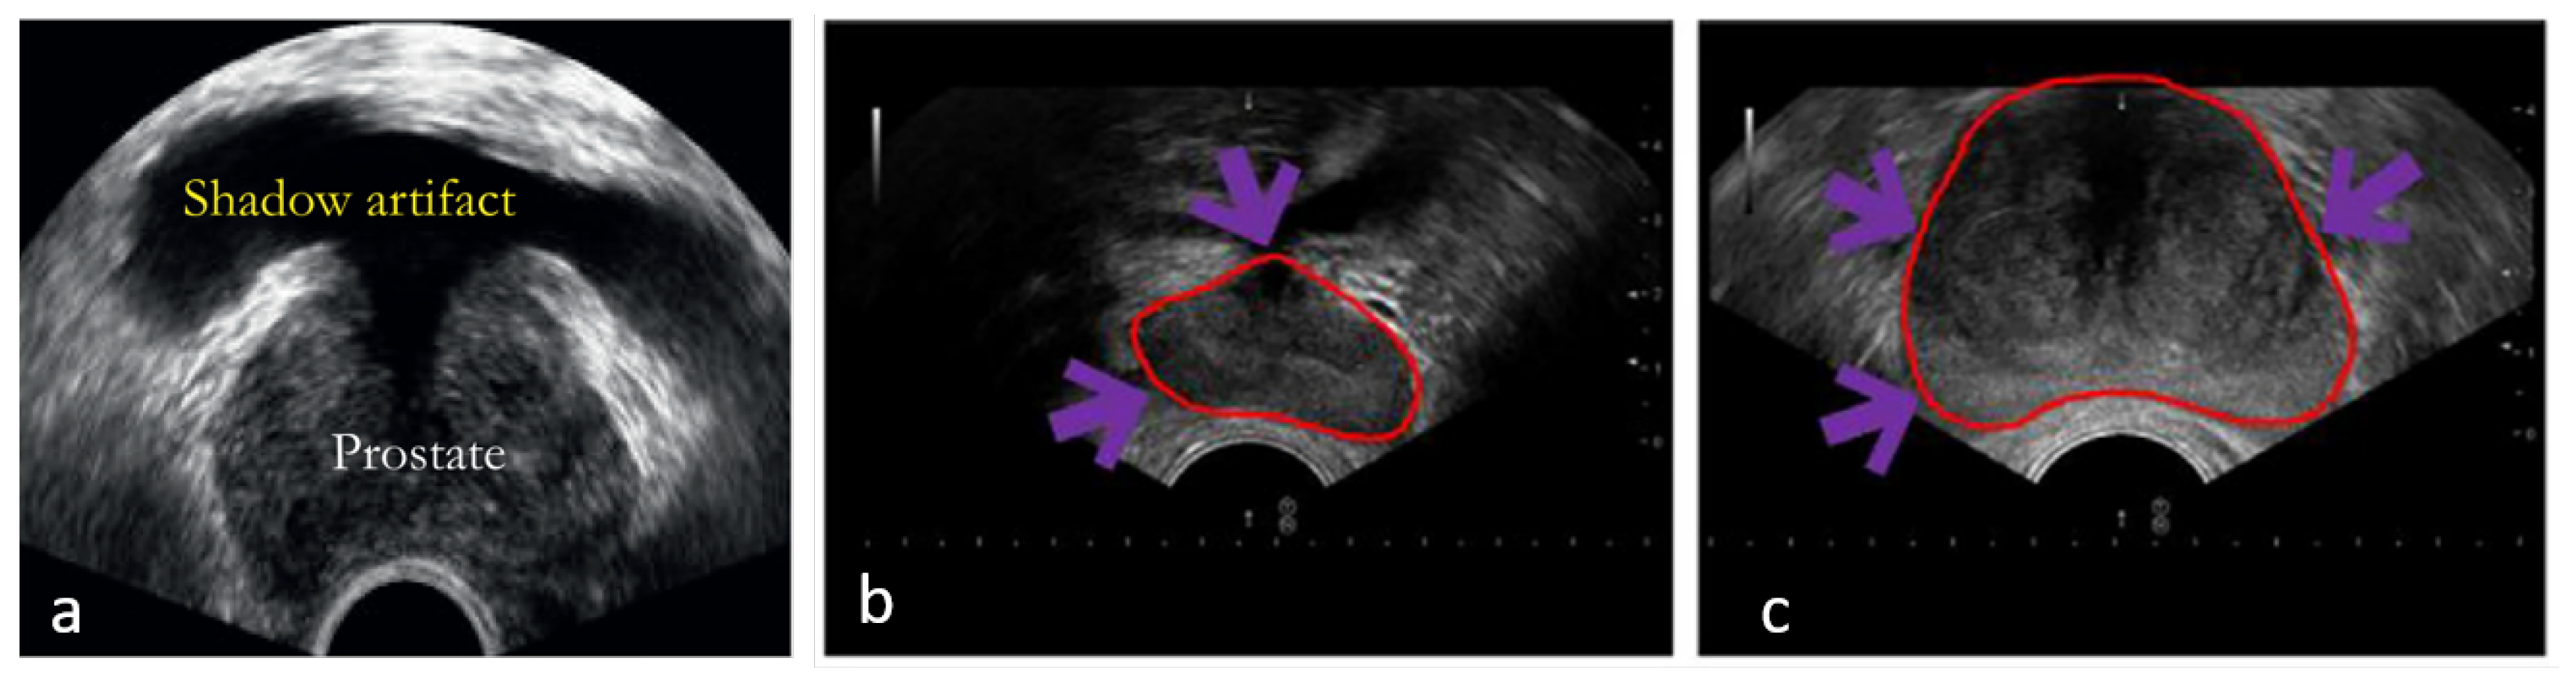

3.1. Ultrasound Pre-Processing Techniques

Pre-processing techniques aimed at improving image readability have been extensively explored to address imaging artifacts inherent in US, which often lead to inaccurate prostate segmentations such as shadow (Figure 3a) and low contrast between the prostate and surrounding structures (Figure 3b-c). Dark areas, known as acoustic shadows, can arise from structures with high echogenicity, such as bones or calcifications. To tackle this, Xu et al. (2022) [39] introduced two novel mechanisms to help networks handle shadow regions at both the image and feature levels. Shadow artifacts were artificially added to training images to enhance the diversity of shadows in the dataset, serving as an innovative data augmentation strategy to increase network robustness on prostate images with shadow artifacts. The authors simulated artifacts by extracting shadow regions from other images using soft thresholding and created augmented training data by fusing these shadow artifacts with other images. Furthermore, shadow features were subtracted from the feature maps, creating a feature space that ignores shadow regions, similar to a systematic drop-out layer. This approach encourages the model to learn the prostate boundary using the remaining shadow-free features. When these methods were added to a traditional U-Net architecture, the results showed an increase in Dice Similarity Coefficient (DSC) by 1.29% and a reduction in Hausdorff Distance (HD) by 0.33 mm.

Figure 3. Example TRUS images in (a) with shadow artifacts in yellow arrows: Adapted from Anas et al. (2018) [20], with permission from Elsevier., and in (b-c) with missing/blurry boundaries in purple arrows: Adapted from Hassan et al. (2022) [40], with permission from Elsevier.